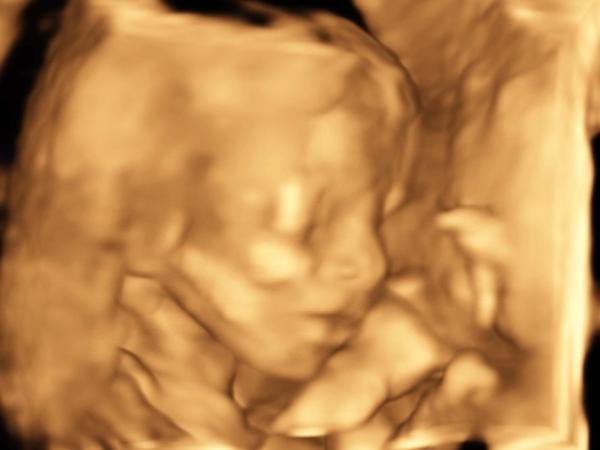

@katariiinkaa Jejoo bubáčik ako sa na tej druhej schováva to je zlaté 😅🥰

Anoo, najprv moc nechcela spolupracovať 😀 odporučili mi dať si pred sonom niečo sladké alebo džús, aby bola živšia. Fakt to bol krásny zážitok 🙏 Presne po tomto ultrazvuku zo mňa aspoň ako tak opadol ten prvotný stres z toho či je všetko v poriadku. Ono na každom tomto veľkom utz sa rieši niečo iné, moja gyn napr. posiela v každom trimestri do sono centra 🙂 preto sme vlastne aj boli. Zároveň aj muž konečne videl drobčeka, veľmi sa mu to páčilo.

@kiki68 ahoj, nemáš prosím ťa náhodou fotku ako to vyzeralo na tom morfo ultrazvuku? Som riadne zvedavá čo sa za tie 2 mesiace zmenilo a aku bude drobec vyzerať ❤️